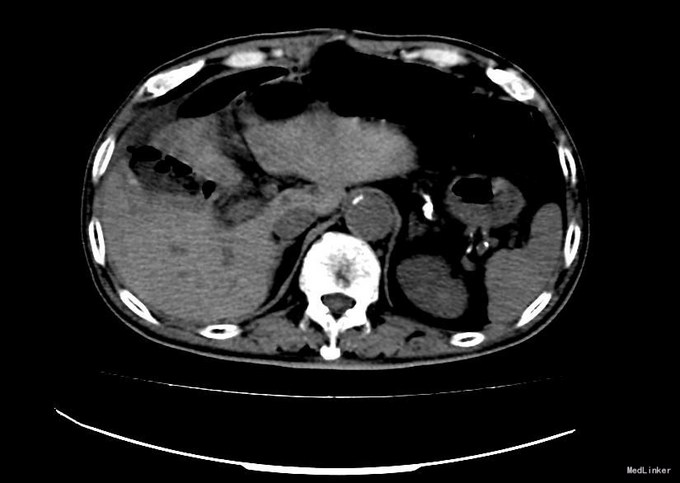

查体:右上腹轻压痛,无反跳痛、肌紧张。墨菲氏征弱阳性。 辅助检查:腹部CT:胆囊体积增大,壁增厚,以胆囊底部为著,增强扫描可见轻度强化,胆囊周围可见积液。MRI:胆囊增大,壁增厚,壁内可见多发结节状低信号灶。胆囊内可见泥沙样短T2信号影。